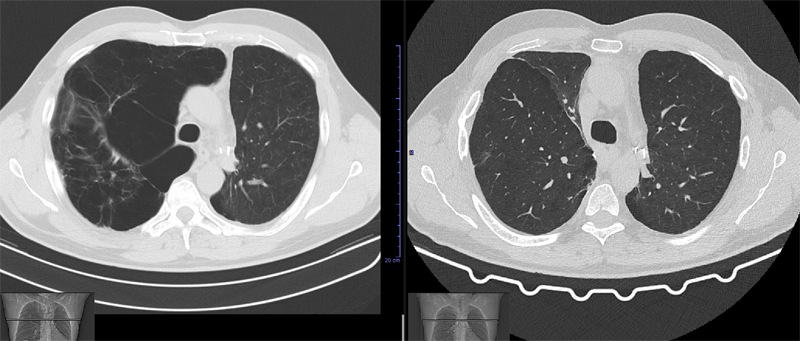

"Qui dice che hai delle bolle nei polmoni, che forse sono congenite ma che si sono aggravate man mano Ora vivi a Messina in una casa umida, dove c'è un deumidificatore che non accendi perché. L’ enfisema polmonare è un malattia dei polmoni provocata da un danneggiamento degli alveoli in essi contenuti La causa più comune risiede nell’inalazione di sostanze dannose contenute per esempio nel fumo di sigaretta, nell’aria inquinata o nelle esalazioni di certi impianti industriali. Il pneumotorace è una patologia ad esordio improvviso caratterizzata dalla presenza di aria nello spazio pleurico (cioè nello spazio virtuale tra i due foglietti pleurici che rivestono il polmone e la parete toracica) È causata dalla rottura di una bolla polmonare per cui l’aria si accumula nel cavo pleurico togliendo spazio al polmone con conseguente rischio.

Il pneumotorace è una patologia ad esordio improvviso caratterizzata dalla presenza di aria nello spazio pleurico (cioè nello spazio virtuale tra i due foglietti pleurici che rivestono il polmone e la parete toracica) È causata dalla rottura di una bolla polmonare per cui l’aria si accumula nel cavo pleurico togliendo spazio al polmone con conseguente rischio. Bolle prendere il posto di tessuto sano distrutta da enfisema, riducendo l'efficienza dei polmoni Definizione Il termine "bolloso" si riferisce a sacche d'aria allargata nei polmoni conosciuti come bolle, secondo il dottor Net UK. Rantoli secchi nei polmoni Sibili asciutto si verificano durante il passaggio dell'aria attraverso i bronchi nel lume del quale v'è una sufficientemente densi contenuti (spessa espettorato viscoso), e attraverso il lume con un ristretto causa bronchi di mucosa gonfiore, spasmo delle cellule muscolari lisce o di crescita tessuto della parete bronchiale neoplastico.

Bolle) cavità d'aria inferiore a 1 cm, situato nell'interstizio e sede subpleurica e bolle formazione di aria più di 1 cm di diametro, le cui pareti sono allineate con l'epitelio alveolare L'esatta prevalenza dell'enfisema bolloso non è definita, ma è noto che questa malattia causa pneumotorace spontaneo nel 7080% dei casi. Il tumore, che inizialmente si sviluppa nel rivestimento interno della vescica, può diffondersi al muscolo che la circonda e poi raggiungere i linfonodi, per via linfatica, e altri organi come polmoni, fegato, ossa, attraverso il circolo sanguigno Quando si diffonde a distanza è chiamato tumore metastatico della vescica. Bolle prendere il posto di tessuto sano distrutta da enfisema, riducendo l'efficienza dei polmoni Definizione Il termine "bolloso" si riferisce a sacche d'aria allargate nei polmoni noto come bolle, secondo il dottor Net UK.

La progressiva disgregazione delle pareti degli alveoli e dei bronchioli porta alla formazione in entrambi i polmoni di vere e proprie bolle, che possono avere un diametro da pochi millimetri a diversi centimetri in altre parole l’aria rimane intrappolata nei polmoni e questo riduce la capacità respiratoria del paziente. Le bolle d'aria sono piccole vesciche piene d'aria che si formano sull'esterno rivestimento dei polmoni A volte, queste bolle d'aria si rompono e rilasciano aria nello spazio pleurico, causando il collasso del polmone Ciò può derivare da cambiamenti nella pressione dell'aria Le bolle d'aria di solito non sono un segno di malattie o altre. Enfisema polmonare sintomi iniziali subdoli e lievi!.

Io fumo parecchio tra l'altro. Il rischio è invece maggiore con una via ev centrale Le bolle d'aria più piccole tendono a dissolversi in circolo e pertanto sono del tutto innocue Piccole quantità di aria non danno luogo a sintomi facilmente individuabili, ma secondo alcuni autori anche queste "microbolle" potrebbero avere alcuni effetti negativi. La progressiva disgregazione delle pareti degli alveoli e dei bronchioli porta alla formazione in entrambi i polmoni di vere e proprie bolle, che possono avere un diametro da pochi millimetri a diversi centimetri in altre parole l’aria rimane intrappolata nei polmoni e questo riduce la capacità respiratoria del paziente.